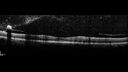

49 year old man with vision loss in the right eye for 2 weeks. VA 20/40 OD, 20/63 OS. DM x 15 years and HTN.